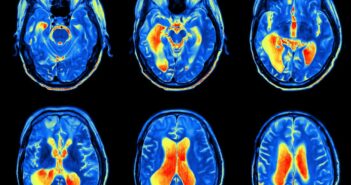

A Semmelweis Egyetem Reumatológiai és Immunológiai Klinikán dolgozó PhD-hallgató, dr. Gunkl-Tóth Lilla a nehezen kezelhető…